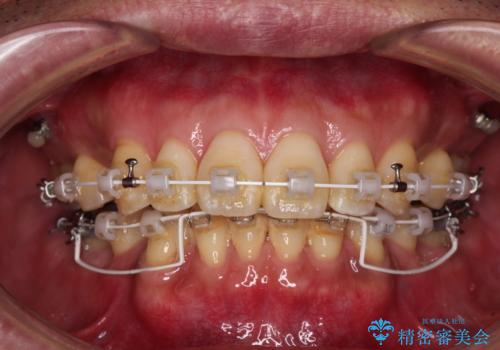

- 口元の突出感を気にして来院された患者様です。

強い咬合力と上顎前歯の傾斜により前歯が突出し、唇が閉じにくい状況であったため、上下左右の第一小臼歯4本を抜歯し、ワイヤー装置にて矯正治療を行うこととしました。

非常に咬合力が強いため、抜歯したスペースが閉じるのか不安でしたが、順調に歯が移動し、予定よりも早く治療を終えることができました。